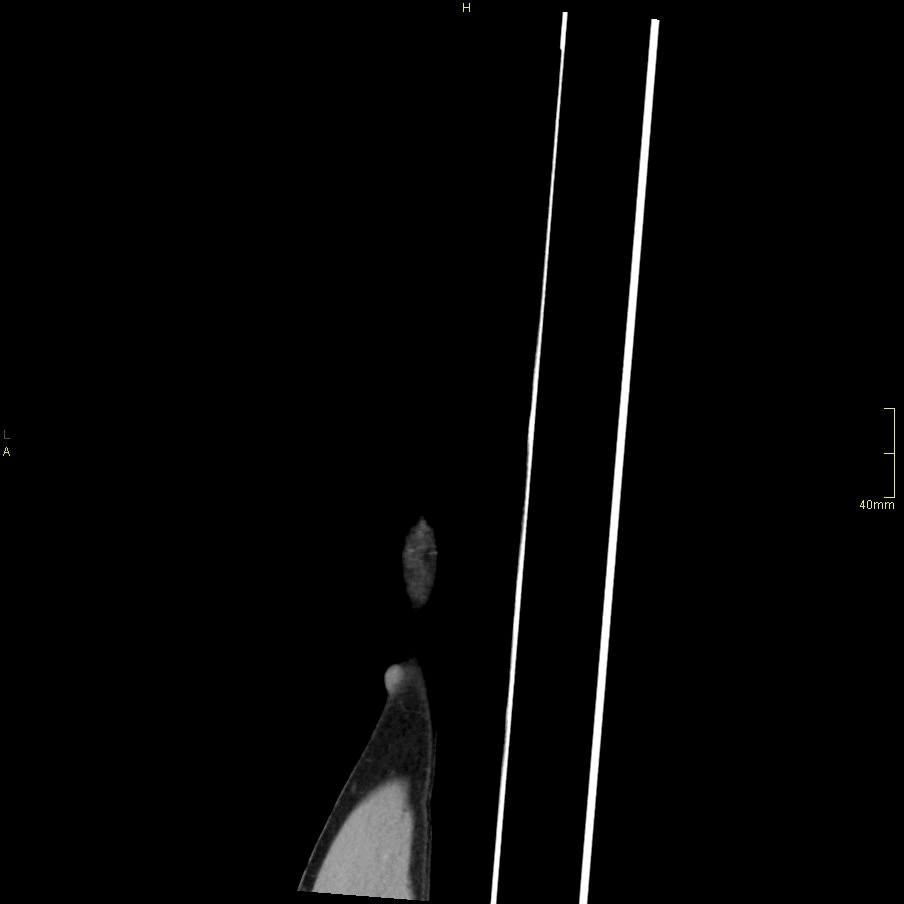

CT Humerus Contrast- Soft tissue window (sagittal)

CT Humerus Contrast- Bone window (sagittal)